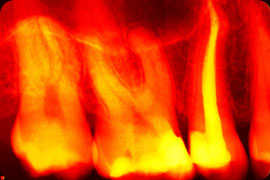

Digitales Röntgen ist ein bildgebendes Verfahren, bei dem nicht ein herkömmlicher Röntgenfilm belichtet wird, sondern eine spezielle Folie oder ein Röntgensensor die von einem Computer abgenommen werden. Das Röntgenbild kann anschließend auf dem Monitor sichtbar gemacht werden.

Digitales Röntgen wird in der Zahnmedizin zur Diagnose und zur Verlaufskontrolle vorgenommen. Besonders bei Karies kann digitales Röntgen erkrankte Stellen sichtbar machen, die bei normaler Betrachtung im Mund noch nicht erkennbar sind. Auch vor Behandlung der Parodontitis, bei einer Wurzelbehandlung und vor Einsetzen von Kronen oder dem Ziehen von Zähnen ist das Anfertigen einer Röntgenaufnahme eine wertvolle Hilfestellung. Es können einzelne Zähnen, begrenzte Kieferbereiche, aber auch eine umfassende, so genannte Panoramaaufnahme (OPG) angefertigt werden.